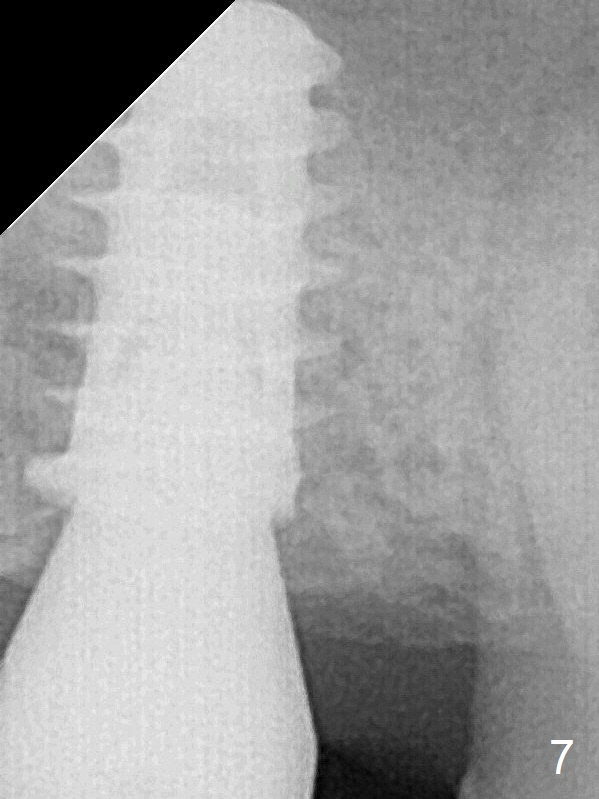

A 5.5x9 mm implant is placed evenly subcrestal (Fig.4).  The patient returns for impression 6 months postop (Fig.7).